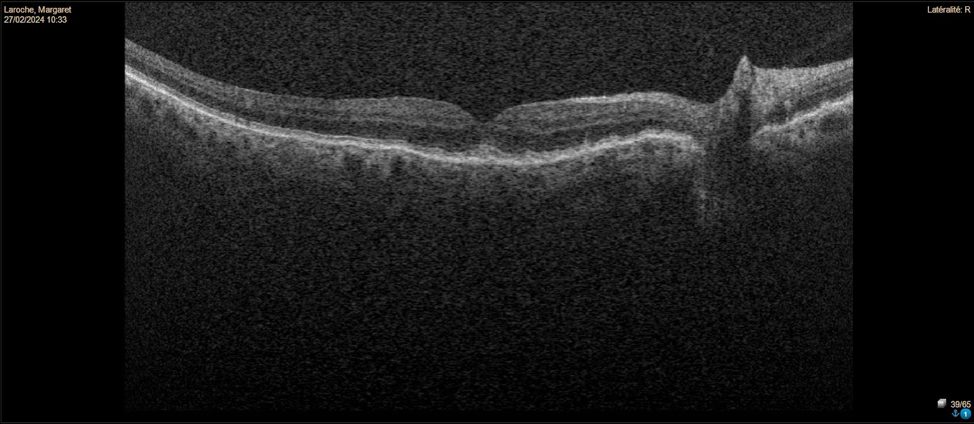

This patient has peripapillary choroidal neovascularization (CNV) in the left eye. Fundus photos reveal drusen and pigmentary changes consistent with dry AMD in the right eye. The left eye shows peripapillary atrophy suggesting a chronic process. OCT imaging of the right eye shows drusenoid pigment epithelial detachments (PEDs), while the left eye has a fibrous PED with overlying subretinal fluid extending close to the parafoveal area. Peripapillary CNV can fluctuate over time but is usually self-limited without foveal involvement. Observation is recommended, along with advising the patient to monitor vision with an Amsler grid.